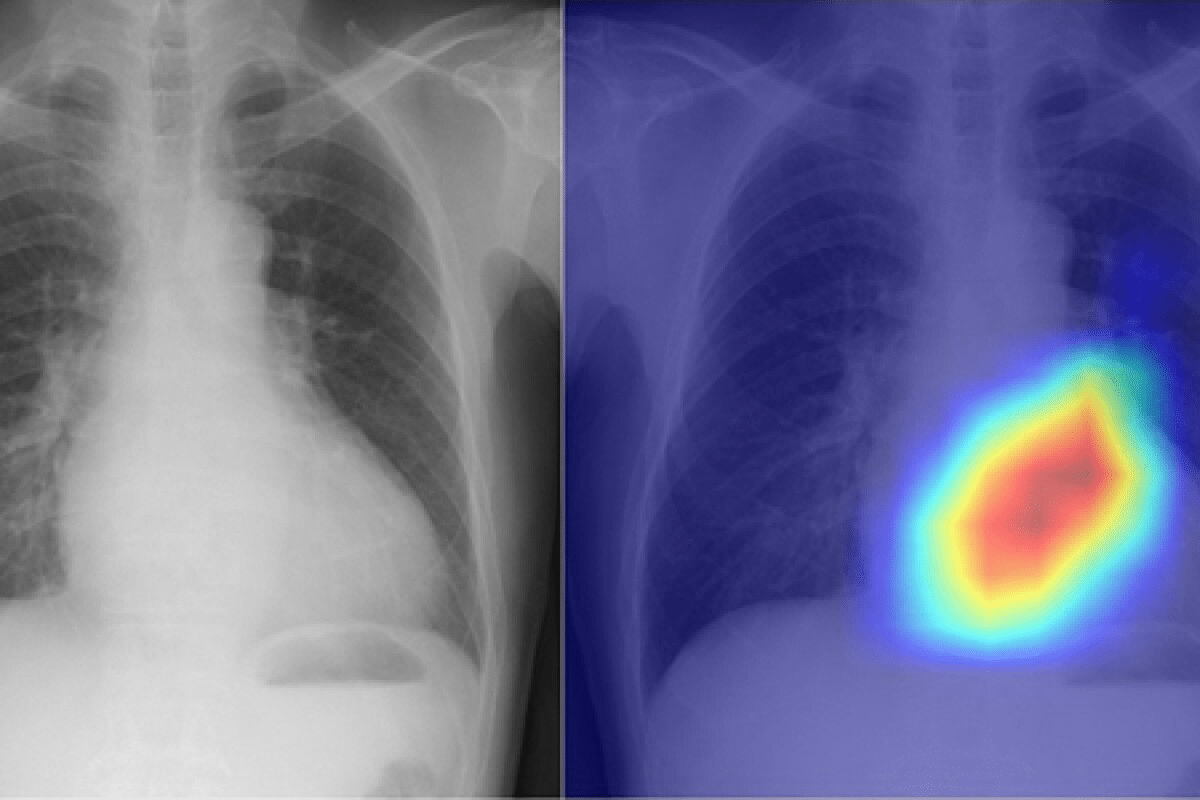

Advanced machine learning approaches are improving pneumonia detection on chest X-rays. Some studies show accuracy rates over 97%. This helps doctors make better decisions.

Machine Learning Applications

Machine learning (ML) is being used more in chest X-ray analysis for finding pneumonia. These ML algorithms learn from big sets of images. They look for patterns linked to pneumonia. The good things about ML in diagnosing pneumonia include:

Research shows ML can be as good as or even better than doctors at spotting pneumonia on X-rays.

Artificial Intelligence Accuracy Rates

Artificial intelligence (AI), mainly deep learning, is very promising for reading chest X-rays for pneumonia. AI can quickly look at images and give detailed reports on lung issues. Recent studies show AI can spot pneumonia with over 97% accuracy. This is a big step forward in finding diseases.